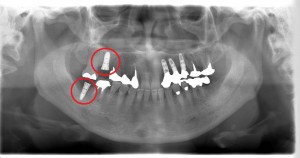

56歳 女性 インプラント症例

56歳 女性 M.H様

左上の前歯3本が歯周病で抜けてしまったため、インプラント治療を希望し来院された患者様です。

3本のインプラント施術を行いました。

その後、右下の1番奥の歯と右上の奥から2番目の歯が歯周病によって、抜かなければならなくなったため入れ歯・ブリッジ・インプラントを欠損部の治療法としてご提案した結果前回の治療の結果に満足されたため、今回もインプラント治療を行うことにしました。